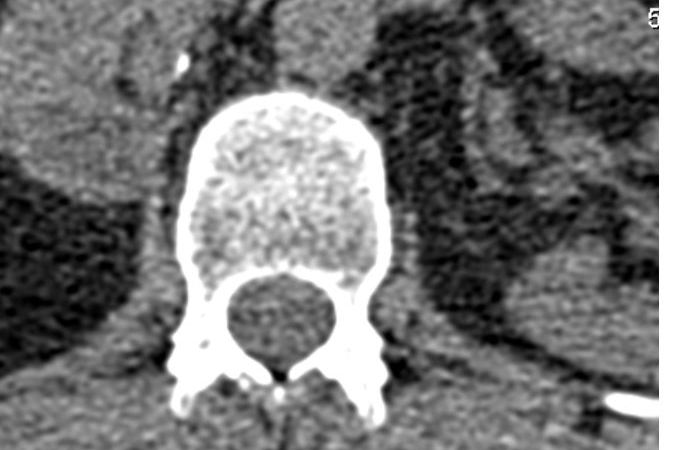

Then there is the other me on Twitter . BoariJ. Boari is the flap of bladder that was constructed twice to try to join up to my right kidney. Not for the squeamish . BoariJ tries to raise awareness, cheer the success of incredibly brilliant clinicians and patients, who despite all odds seem to be so positive so forward looking and taking the twitteri by storm. Some of the consultants I know tweet, support each other and ponder weird blurry images of god knows what bit of the urinary tract.